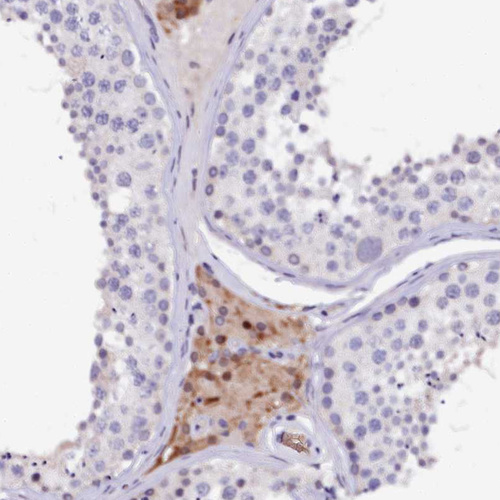

Immunohistochemical staining of human testis shows moderate nuclear/cytoplasmic positivity in Leydig cells.